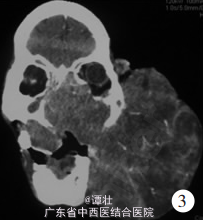

查体:专科检查:面部有一约 24 . 5 cm × 16 . 0 cm × 12 . 0 cm大小的结节状肿物,基底位于左面部,肿瘤表面有皮肤覆盖,可见扩张的血管, 部分皮肤破溃、 流脓、 结痂,有臭味( 见图 2 ) ;右眼失明,左眼及左侧嘴角被肿瘤遮挡,移开肿瘤后检查左眼视力为光感;颈部未触及增大淋巴结。 辅查:行鼻窦 CT 检查示 ( 见图 3 ) 。 鼻窦增强 MRI 检查示:( 见图 4 ) 。 查血红蛋白 106 g / L,完善 X 线胸片、头颈部及腹部 B 超检查均未发现肿瘤转移征象。